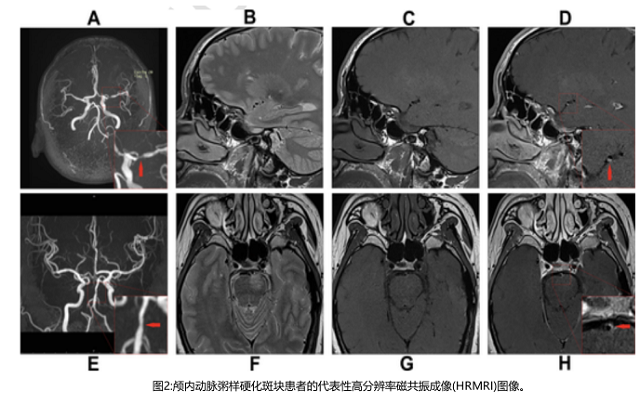

高分辨率磁共振成像(HRMRI),一種處理血流和血管壁對比的無創(chuàng)成像技術(shù),作為一種可靠的可視化血管壁形態(tài)和病理的成像方法,在無創(chuàng)體內(nèi)分析中獲得了突出的地位。HRMRI突破了傳統(tǒng)體內(nèi)血管檢查技術(shù)的局限性,為我們提供了有關(guān)動脈粥樣硬化組成的信息,如炎癥、壞死核心的存在和斑塊內(nèi)出血。HRMRI上顱內(nèi)斑塊的異質(zhì)性增強(qiáng)是斑塊不穩(wěn)定的標(biāo)志,與有癥狀的顱內(nèi)動脈粥樣硬化患者近期的缺血事件和卒中復(fù)發(fā)密切相關(guān)。該研究基于HRMRI研究HDL亞組分與顱內(nèi)大動脈粥樣硬化斑塊特征之間的關(guān)系。

病變部位定義為由MCA動脈粥樣硬化病變引起的管腔狹窄最嚴(yán)重的水平(圖2)。通過血管-腦脊液界面自動計算血管面積(VA)。管腔面積(LA)由血管-血液界面計算。選擇斑塊最厚的切片來測量直徑。壁面積(WA)計算為血管面積減去管腔面積。斑塊面積為病變部位的WA減去參考部位的WA。斑塊負(fù)擔(dān)計算為斑塊面積/病變部位血管面積× 100%。狹窄率公式為(病變部位1-LA /參考部位)× 100%。重構(gòu)指數(shù)(RI)是指病變部位血管面積與參考部位血管面積之比。陽性重構(gòu)(PR)定義為RI > 1.05;負(fù)重構(gòu)(NR)定義為RI < 0.95;中度重構(gòu)定義為RI在0.95 ~ 1.05之間。